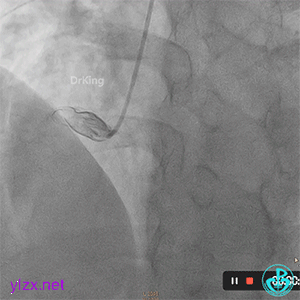

处理前降支病变,导丝Pilot 50通过LAD病变到达远段,沿导丝送入穿通导管至远段,回抽有血,造影提示在真腔。

PTCA球囊扩张后无前向血流,以硝普钠反复行冠脉内局部药物释放治疗术。

复查造影提示LAD血流恢复TIMI血流2-级。